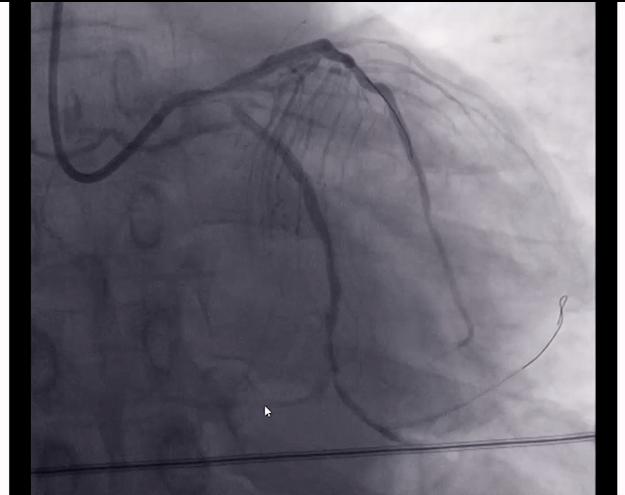

根据这些情况,我们决定首先打通紧急闭塞的回旋支。我们手术的时候,把导丝通过了闭塞的病变,经过一系列的扩张,放置了两枚支架,这个闭塞的回旋支就被打通了。

这时候患者的右侧血管还没有打通,但是老杨血压偏低,一般来说心功能较差,如果打通右侧的血管,需要更多的时间和造影剂。为了避免患者不能耐受情况的发生,仅仅处理了回旋支闭塞,结束了手术。等老杨恢复一定时间之后,再考虑处理右侧的病变。

4.对于冠心病患者,我们只有进行规范化的、综合性的康复的治疗,才会有一个良好的结果。(图片是患者打通闭塞血管,放置了两根支架的一个情况。同时我们还可以看到右边这根血管闭塞出现的一个侧枝循环,也就是左侧的这些血管,和右侧血管远端联通的一个影像,这就是自身进行的侧支循环的建立。)